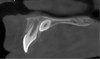

Fig 7. This test object was scanned with a desktop laboratory scanner and CBCT device. The full-metal molar crown (circled) was used to demonstrate the effects of the metal artifacts produced by the CBCT and the outcome of the implementation of a metal artifact reduction algorithm (MAR).

Figure 7

Fig 8. Thin slice at the level of the metal crown in Fig 7 with no MAR used. The outline relates to the stone model of the teeth. Blooming due to metal artifacts can be noted.

Figure 8